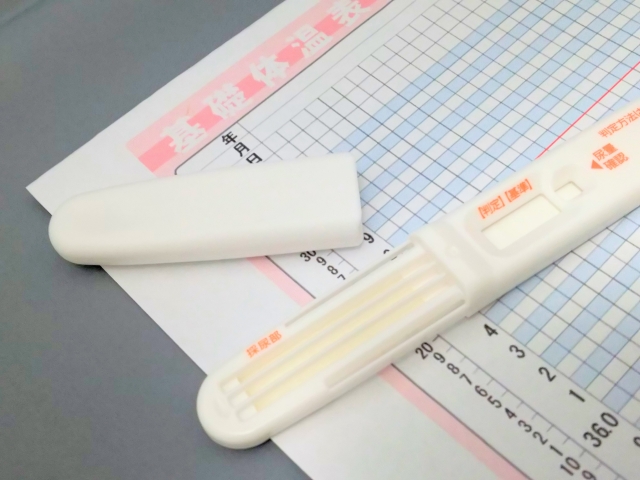

妊活をする理由とは?妊娠しやすいタイミングを知っておく妊活をして子供を授かりたい夫婦にとって大切なことは、妊娠しやすいタイミングを知って効果的に妊活に励むことです。若い夫婦ならば自然に妊娠するかもしれませんが、高齢妊活をする夫婦にとっては妊娠しやすいタイミングを知ることは重要です。妊娠しやすいタイミ...

妊活の現状妊活という言葉が世の中に浸透し始めてから、数年が経過しました。妊娠するために行う活動を総称して妊活と言いますが、今や妊活は、妊娠を希望する多くの女性が経験する重要な活動とも言えるでしょう。妊娠するための活動が必要となった時代の背景には、女性の社会進出があります。男性に負けず、女性も社会に進...